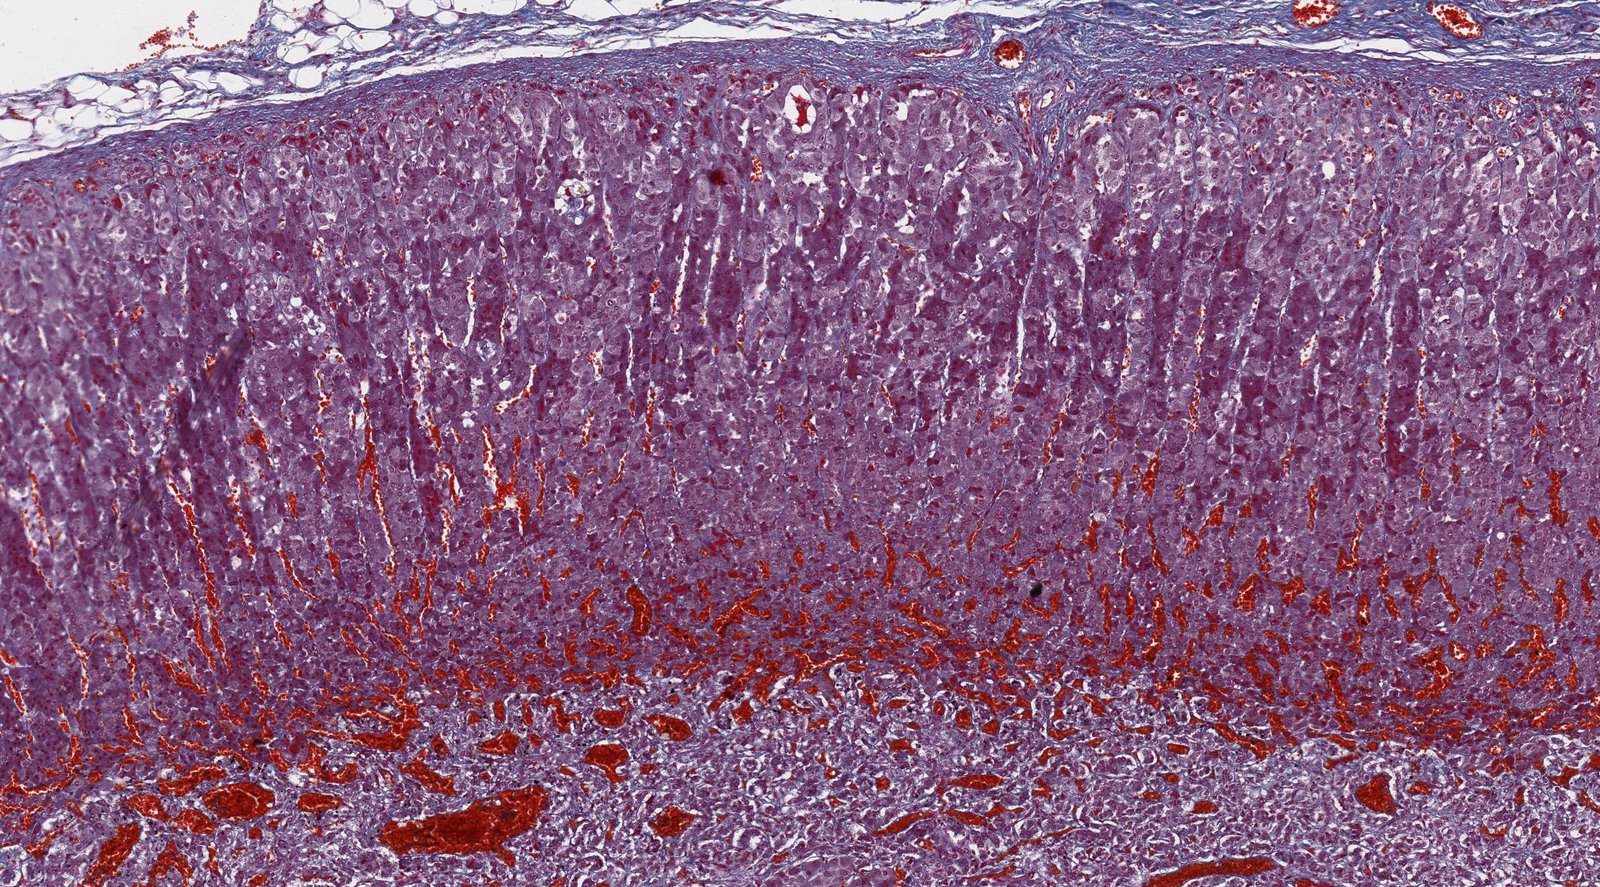

Adrenal medulla

- Overview: : The adrenal medulla is surrounded by the adrenal cortex and made up of modified sympathetic postganglionic neurons. [4]

Organization

- Contains large, irregularly shaped, chromaffin cells with many secretory granules for catecholamine storage

- Arranged in clusters and grouped around fenestrated capillaries

- Tumors originating from chromaffin cells are called pheochromocytomas.

The cells of the adrenal medulla are modified sympathetic cells that are controlled by cholinergic synapses.